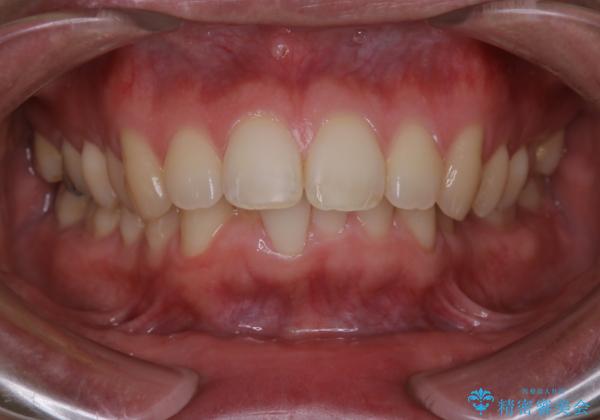

がたつき、口ゴボ(出っ歯)、真ん中のずれを抜歯矯正治療で治す。ワイヤー矯正治療

- 患者様

- 20代男性

- 口元の突出感とがたつきを気にして来院されました。